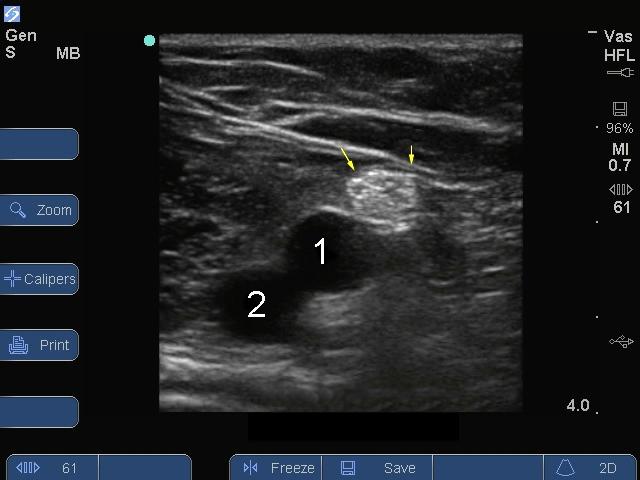

Bild: S Series, Nervus ischiadicus, Popliteal-Gefäße

Pfeile: Nervus ischiadicus

Vene

Arterie